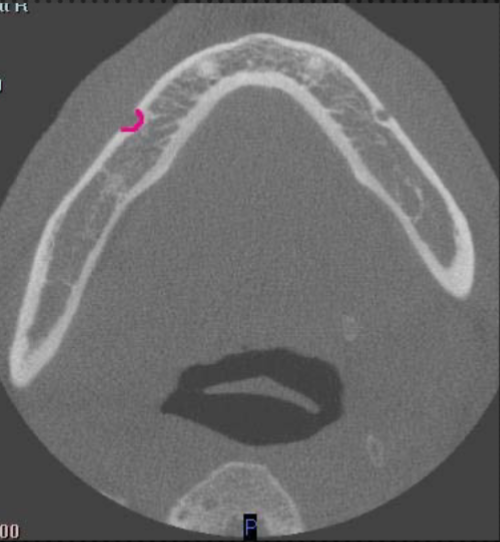

apical of roots

at what level is this